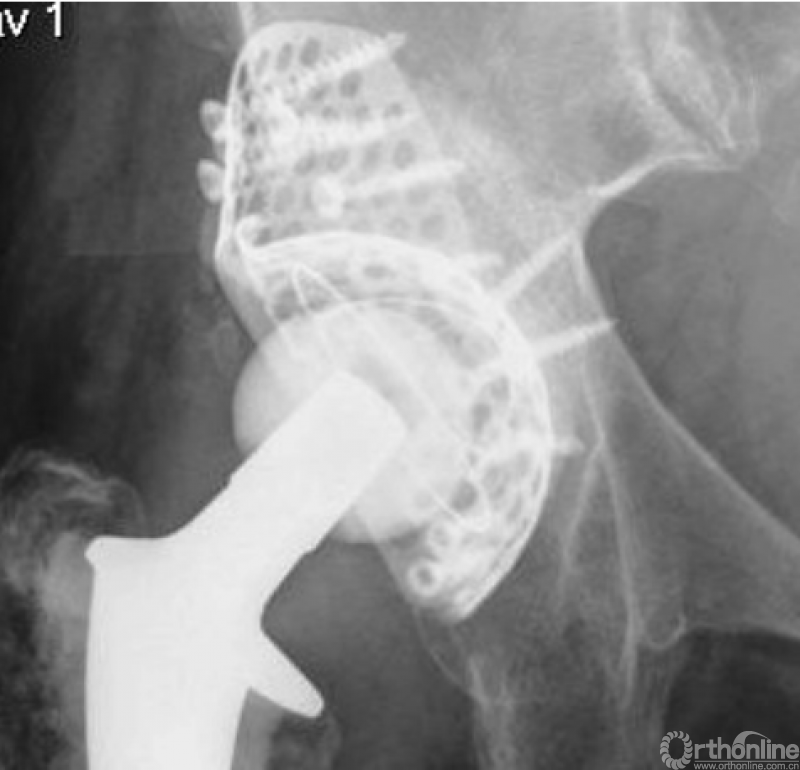

应用此方法治疗AAOS Ⅲ型髋臼侧骨缺损后6年影像学表现

植骨片打压入钛板内,修复了节段性髋臼骨缺损,再植入钛金属外杯加压并稳定植骨床

打压植骨后用4-7枚短钛钉将外杯固定于植骨床之上,再用骨水泥将聚乙烯外杯粘入